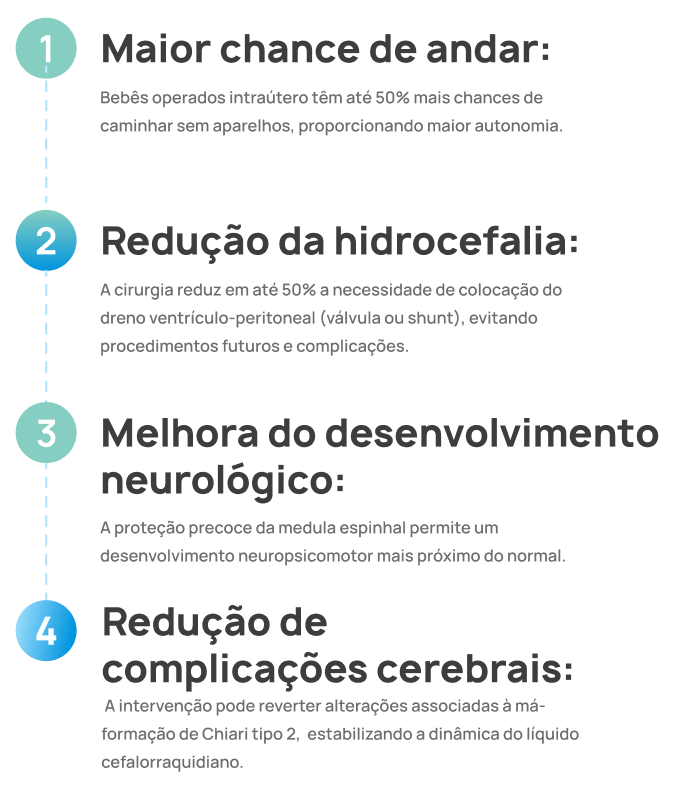

Quais as vantagens da cirurgia fetal?

A cirurgia fetal pode transformar significativamente o futuro do seu bebê, trazendo benefícios cientificamente comprovados, como:

Maior chance de andar:

Bebês operados intraútero têm até 50% mais chances de caminhar sem aparelhos, proporcionando maior autonomia.

Redução da hidrocefalia:

A cirurgia reduz em até 50% a necessidade de colocação do dreno ventrículo-peritoneal (válvula ou shunt), evitando procedimentos futuros e complicações.

Melhora do desenvolvimento neurológico:

A proteção precoce da medula espinhal permite um desenvolvimento neuropsicomotor mais próximo do normal.

Redução de complicações cerebrais:

A intervenção pode reverter alterações associadas à má-formação de Chiari tipo 2, estabilizando a dinâmica do líquido cefalorraquidiano.

Esse benefícios foram comprovados pelo estudo MOMS Trial, referência mundial que embasa nossos procedimentos.